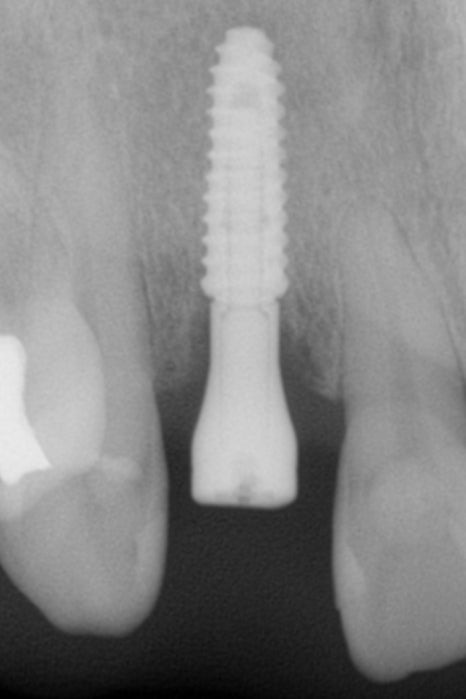

임플란트 식립 후

왼쪽의 임플란트 식립 직후

방사선 영상 검사에서

아주 적절한 위치와 이상적인 방향으로

임플란트가 식립되었음을 알 수 있습니다.

임플란트 식립 수술만큼이나

임플란트 재료도 중요하지 않을 수 없습니다.

임플란트와 뼈가 붙는 '골유착'을

더 빠르고, 튼튼하게 하기 위해

임플란트 표면에 자외선 처리를 한

UV 임플란트를 사용하였습니다.